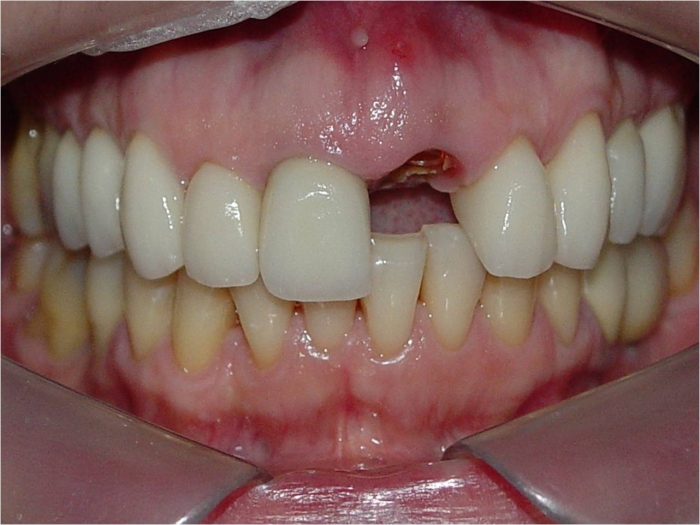

Imagem do dente 21 fraturado